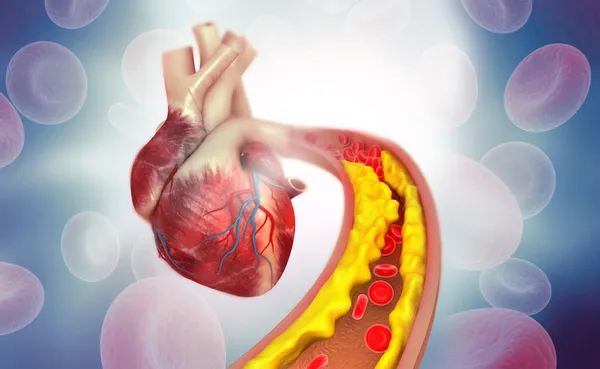

Hareketsiz yaşam tarzı ve yanlış yiyecek seçimleri yüksek kolesterole ve çeşitli kronik hastalıklara neden olabilir. Bazı gıdalar kötü kolesterolü düşürmeye yardımcı olabilir ve bunları günlük beslenmeye dahil etmek önemlidir.

Diyetisyen Garima Goyal, “Kolesterol dünya çapında önemli bir sağlık sorunudur ve yetişkinlerin tahminen %50’si yüksek kolesterol seviyelerinden muzdariptir. Yüksek kolesterol seviyeleri, önde gelen ölüm nedenlerinden biri olan kalp hastalığı riskini artırır” diyor.